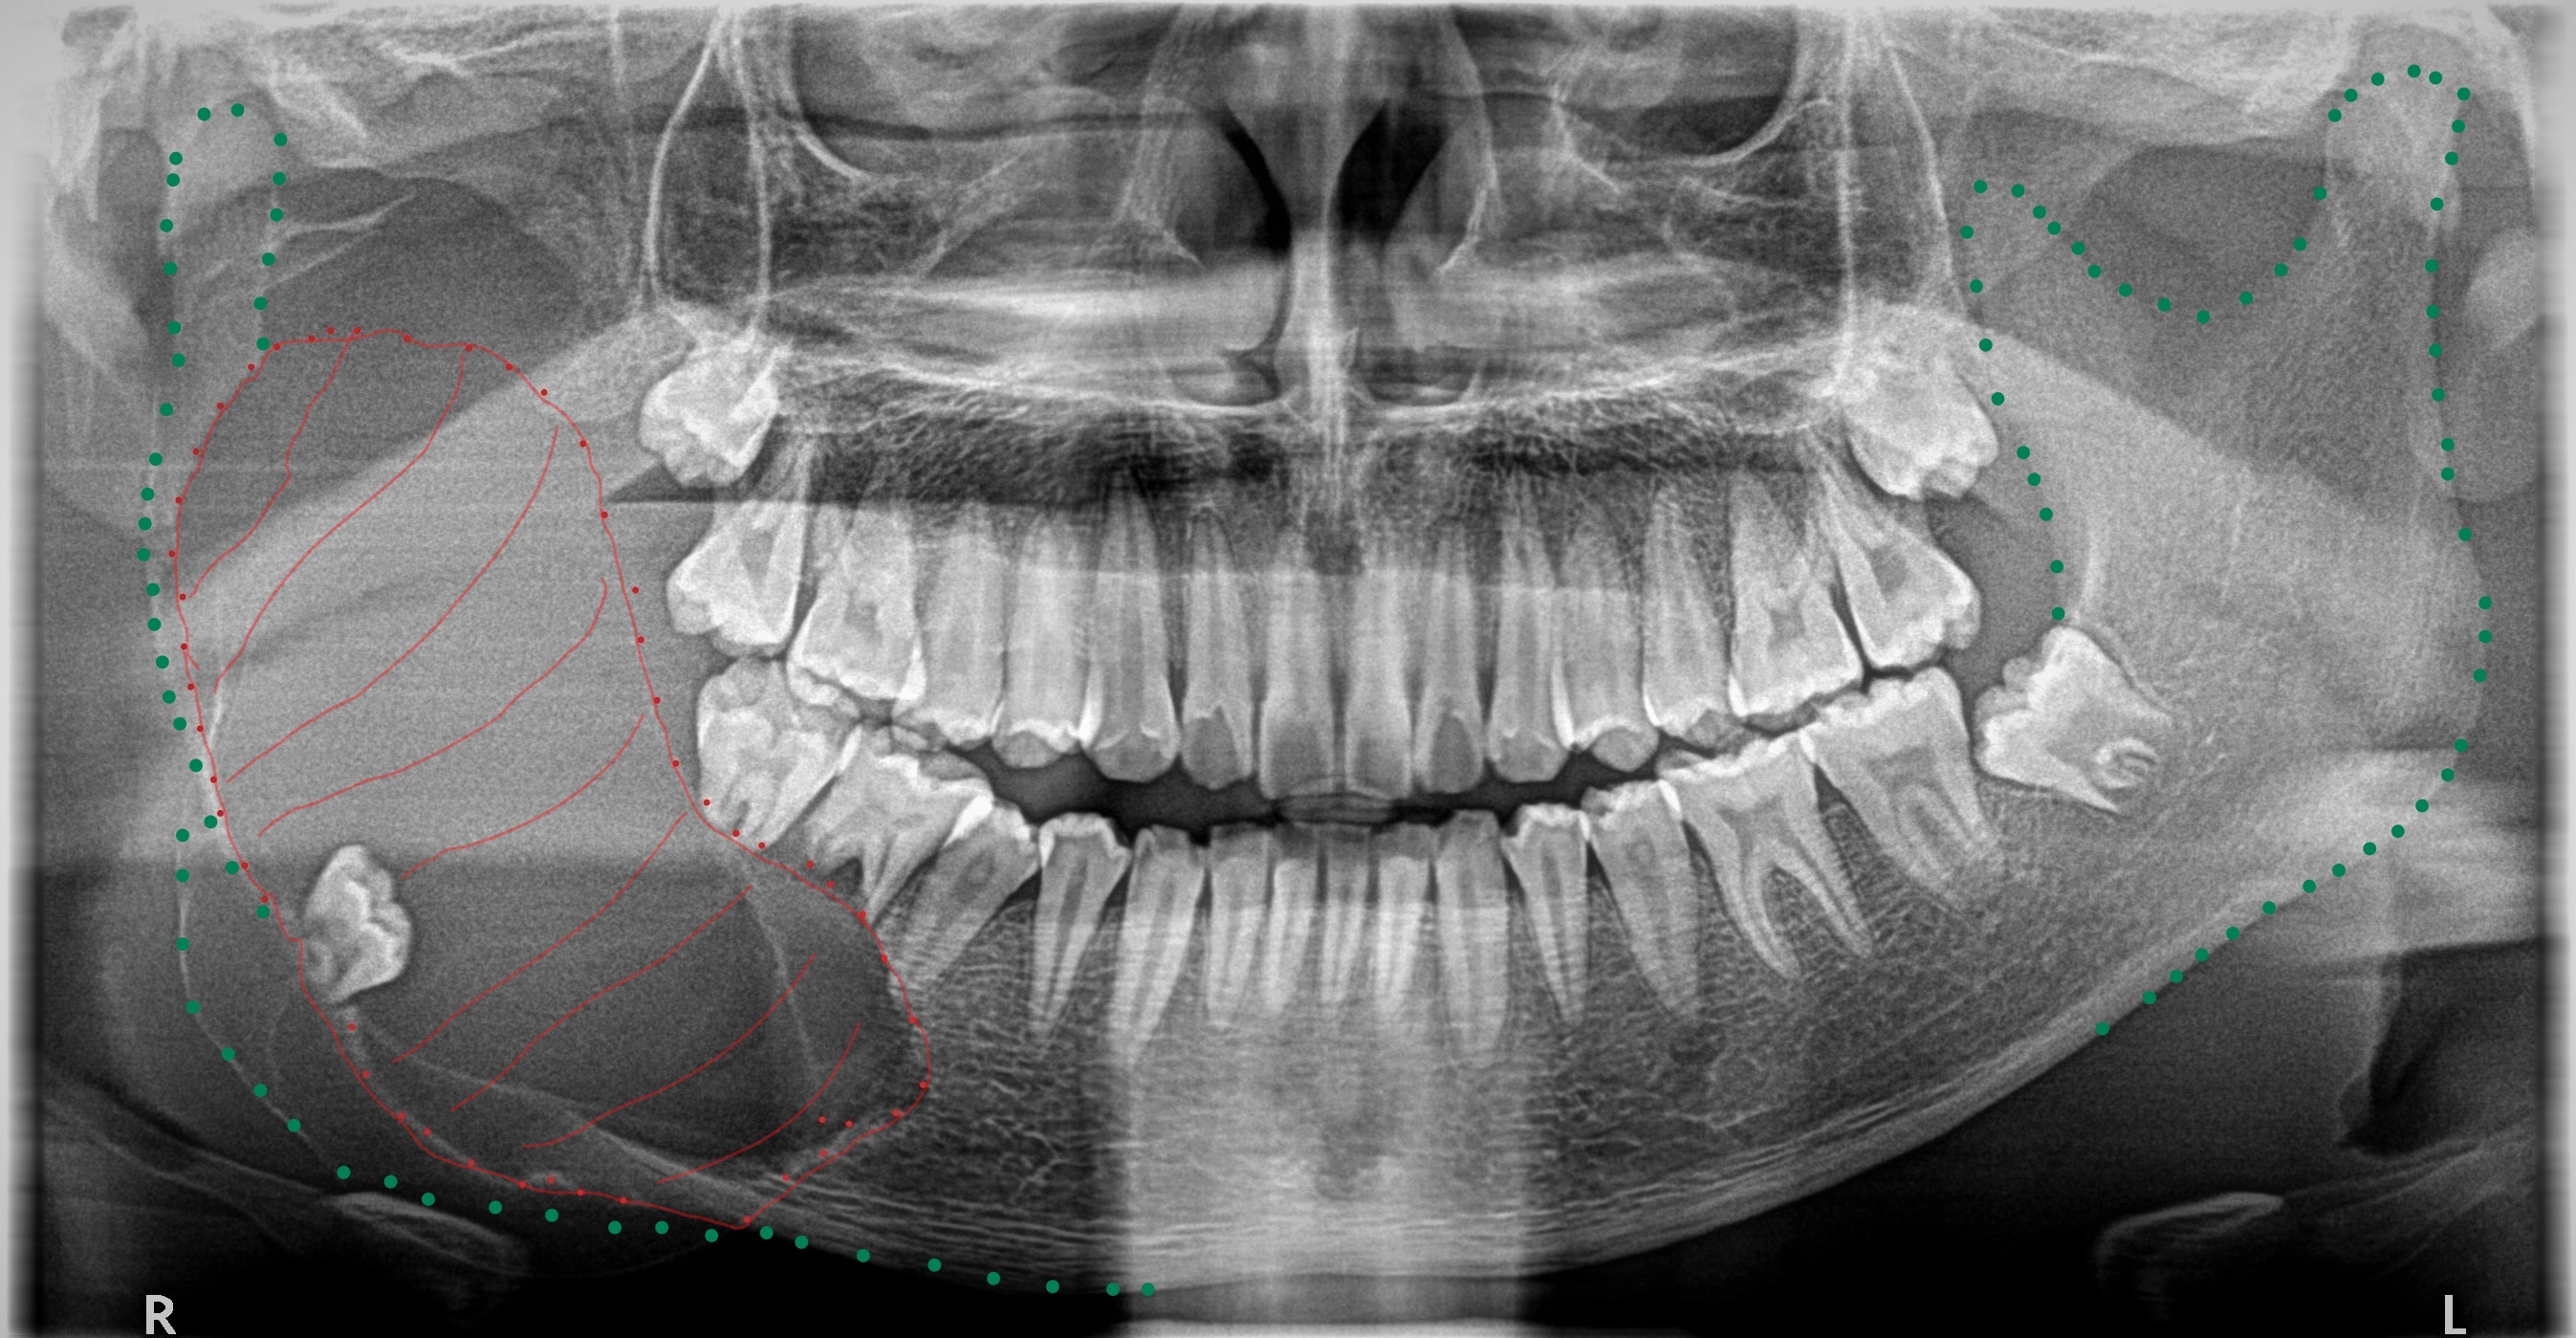

A few days ago, as we were about to close, a 14-year-old boy came in with what looked like a tennis ball in his right cheek. He was not in too much pain, but was very conscious of a large swelling and so wore a hoodie to hide it. I suspected a dental abscess had gone far down the road, but nothing prepared me for what a Panoramic x-ray scan would reveal.

My nurse was in disbelief as she ran into my room to come and have a look at what she thought was a bad x-ray. Right in front of me was the largest tumour I had seen relating to a wisdom tooth. The tumour had grown and pushed the wisdom tooth to the bottom of the jaw and in doing so, had destroyed most of the right jaw. We are looking at a 14-year-old. He will now require massive surgery and jaw reconstruction, if it is possible. Or face permanent disfigurement.

I have marked out the tumour in red and the jaw outline in green, to spread awareness that we must review every patient with a Panoramic x-ray by age 12. Thereafter, every 5 years, to be prudent.